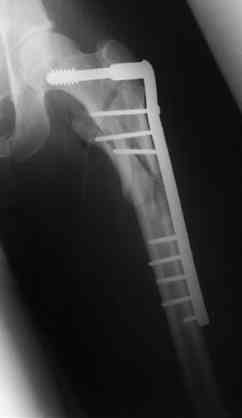

Бедро фиксировал длинной DCS.

По типу бриджинг плэйтин, крюком удалось низвести малый вертел и фиксировать винтом для восстановления медиальной стенки.

> Бедро фиксировал длинной DCS.

А почему не гвоздем закрыто?

ET>> Бедро фиксировал длинной DCS.

AC>А почему не гвоздем закрыто?

Изначально планировался длинный гамма гвоздь , но набор заказывается обычно из Йоханнесбурга, а в этот раз все совпало с новогодними празднованиями и вся жизнь была *парализована* новогодней фиестой:-((, поэтому безуспешно прождав 3-4-5 дней обещанной доставки зафиксировал пластиной- жаль, что так всй случилось У местного

Страйкера сервис ненавязчивый :-))

ET>> По типу бриджинг плэйтин, крюком удалось низвести малый вертел и

ET>> фиксировать

AC>IMHO это лишние трудозатраты, ничего плохого не случается при оставлении малого вертела в покое.

Да, в данном случае с DCS фиксация малого вертела не принципиальна, при разноугольных DHS восстановление задне-медиальной стенки( малый вертел с фрагментом), все же желательно - потенциально нестабильная репозиция (на

важность этой детали указано в Кэмбелле 2003, стр.2877) - шейка укорачивается

В приложении отправляю послеопер. снимки бедра и лодыжки обсуждаемого вчера больного.